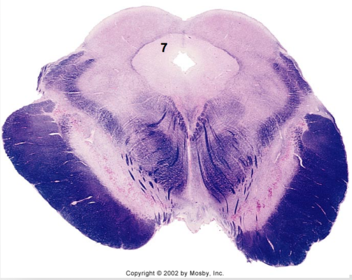

| Facial nerve root fibers - descending | |

| Facial motor nucleus | |

| Interposed nuclei | |

| Medial longitudinal fasciculus | |

| Facial nerve root - internal genu | |

| Abducens nucleus | |

| Lateral vestibular nucleus | |

| Superior vestibular nucleus | |

| Inferior cerebellar peduncle | |

| Superior cerebellar peduncle | |

| Dentate nucleus | |

| Fastigial nucleus | |

| Anterior spinocerebellar tract | |

| Spinal nucleus of V | |

| Spinal tract of V | |

| Middle cerebellar peduncle | |

| Medial lemniscus | |

| Trapezoid body | |

| Ventral trigeminothalamic tract | |

| Superior olive | |

| Longitudinal pontine fibers (corticospinal tract) | |

| Transverse pontine fibers (dark fibers) | |

| Pontine nuclei (pale) | |

| Central tegmental tract | |

| ALS | |

| Principle nucleus of V | |

| Mesencephalic V tract | |

| Trigeminal root fibers | |

| Motor nucleus of V | |